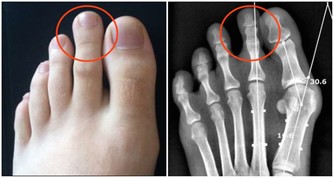

這是腎功能在逐步衰退的信號,有時還會伴隨著腳痛、腰痛、尿頻等症狀,